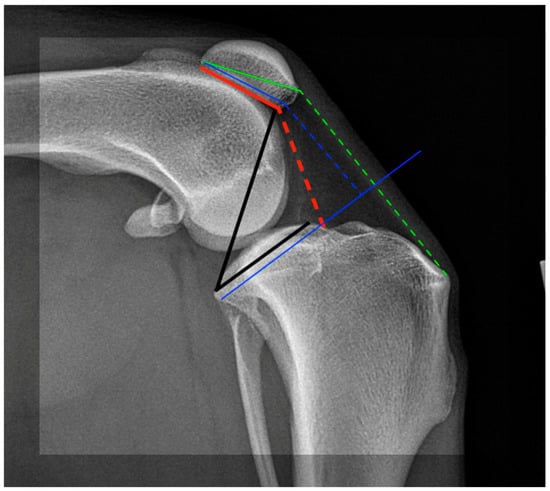

- Bonadio, M.B.; Torres, J.A.P.; Filho, V.M.; Helito, C.P. Plateau-patella angle: An option for assessing patellar height on proximal tibia osteotomy. Acta Orth. Bras. 2016, 24, 127–130. [Google Scholar] [CrossRef] [PubMed][Green Version]

- Slocum, B.; Slocum, T.D. Tibial plateau leveling osteotomy for repair of cranial cruciate ligament rupture in the canine. Vet. Clin. N. Am. Small Anin. Pract. 1993, 23, 777–795. [Google Scholar] [CrossRef] [PubMed]

- Reif, U.; Dejardin, L.M.; Probst, C.W.; DeCamp, C.E.; Flo, G.L.; Johnson, A.L. Influence of limb positioning and measurement method on the magnitude of the tibial plateau angle. Vet. Surg. 2004, 33, 368–375. [Google Scholar] [CrossRef] [PubMed]